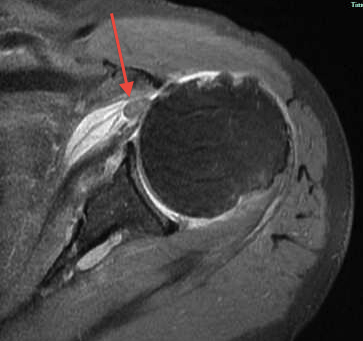

Tendonitis / tendinopathy

Normal

Tendonitis

Tendon thickening / tendinopathy

Sagittal MRI demonstrating severe LHB tendinopathy